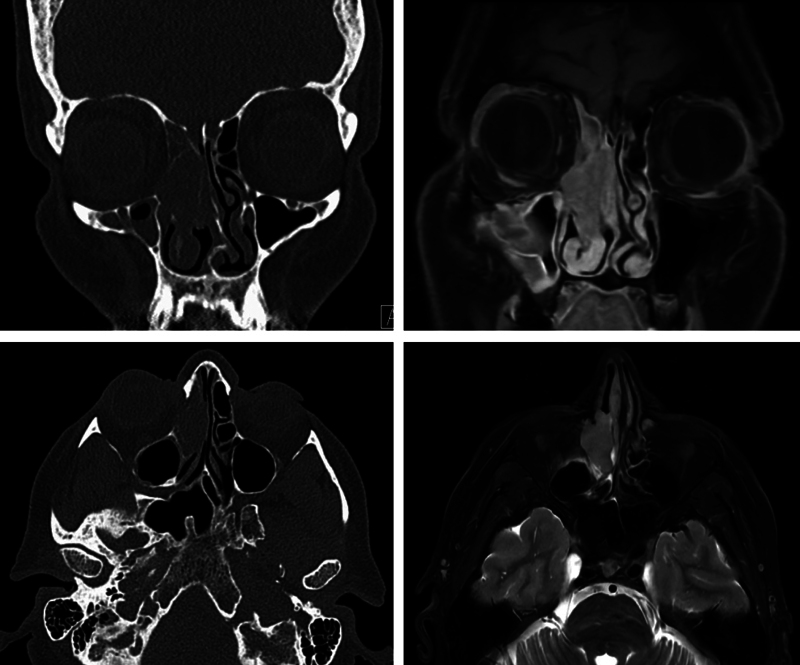

Human papillomavirus (HPV)-associated sinonasal squamous cell carcinoma (SNSCC) (HPV+ SNSCC) is a recently recognized entity that accounts for up to one-third of SNSCC. Although at present these cancers are not routinely tested for HPV, the incidence is increasing and HPV+ SNSCC is associated with superior survival outcomes compared with HPV- SNSCC. Here, we present the case of a patient with HPV+ SNSCC treated with endoscopic resection followed by postoperative radiation and review the literature summarizing epidemiology and management of this disease, with emphasis on the importance of HPV testing in SNSCC.